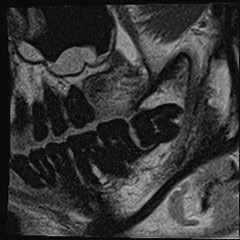

Magnetic resonance imaging (MRI) has been a staple in medicine and dentistry for many years. In dentistry, it serves a somewhat confined role in imaging the temporomandibular joints (TMJ) and occasionally the head and neck, including cysts or tumors. Dental MRI research and publications on these indications, as well as more “traditional” dental imaging tasks such as caries or periapical lesion detection, have progressed steadily since the mid-1980s, followed by a rapid increase in published papers in the early 2020s. These studies have long demonstrated the utility of MRI TMJ and cyst/tumor imaging, as well as the promise of MRI for essentially the entire range of dental imaging indications. Indications include caries, periapical disease, periodontal disease, growth and development/

Proton density (left) and CBCT (right) images of apical lesion and furcation involvement at tooth #2. This tooth was clinically diagnosed with pulpal necrosis and a crack involving the furcation.

Proton density image showing improved image detail provided by dental dedicated MRI coil.

Proton density image of horizontally impacted tooth #17.

Proton density image of TMJ demonstrating anterior disc displacement, disc fold and joint effusion.